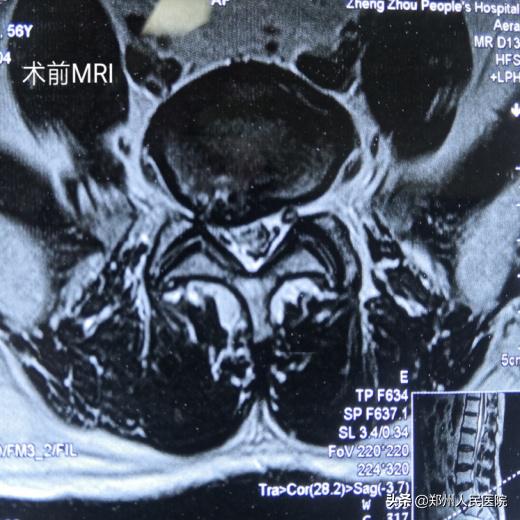

56岁的刘叔有着和小葛一样的困扰,而且他的症状更严重,病程时间更长。腰部疼痛伴右下肢放射痛麻木8年,加重伴间歇性跛行1个月,右足跟、足底及足外侧的皮肤痛触觉减退,右足的跖屈及右足趾背伸肌力也明显下降,平日里连日常遛弯走上几百米都成了奢望。

8年间刘叔曾尝试过针灸、按摩、局部理疗、神经根阻滞等多种保守疗法,但效果欠佳,症状仍然反复发作。

在了解到郑州人民医院东区骨科开展的“UBE技术”可以实现微创的切口,同样能达到开放性手术的减压效果后,他最终下定决心进行手术。

为刘叔进行的“单侧双通道UBE脊柱内镜术”在不足两个小时后顺利结束,术中麻醉效果极佳,出血量只有数十毫升,清晰放大的视野下,突出的髓核及增厚的黄韧带完全摘除,骨性狭窄磨钻安全扩大减压,偶尔出现的小出血点也在射频刀头的控制下立即止血,轻松漂浮的神经根又重新出现了。